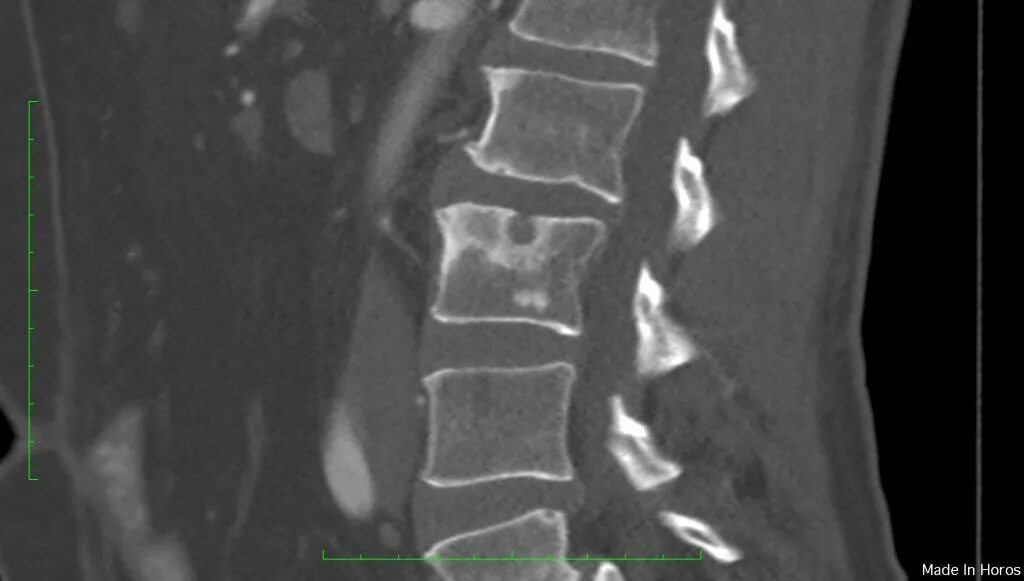

Протрузии шморля